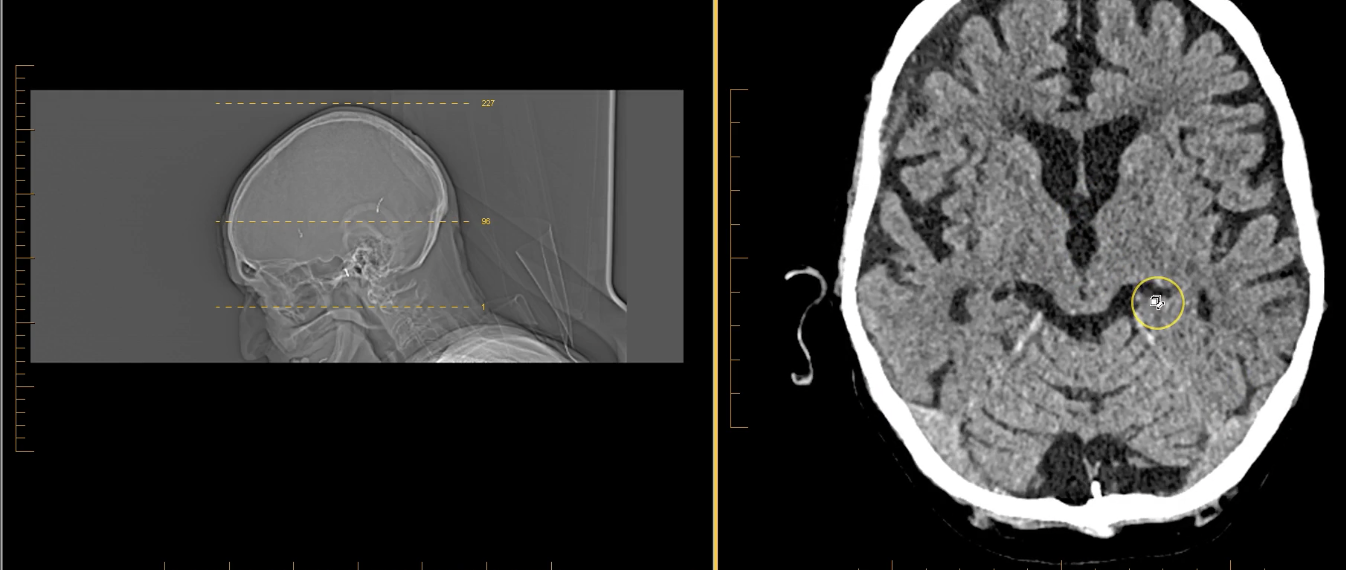

term image

pineal gland- hyperdense. part of endocrine system. secrenes melatonin